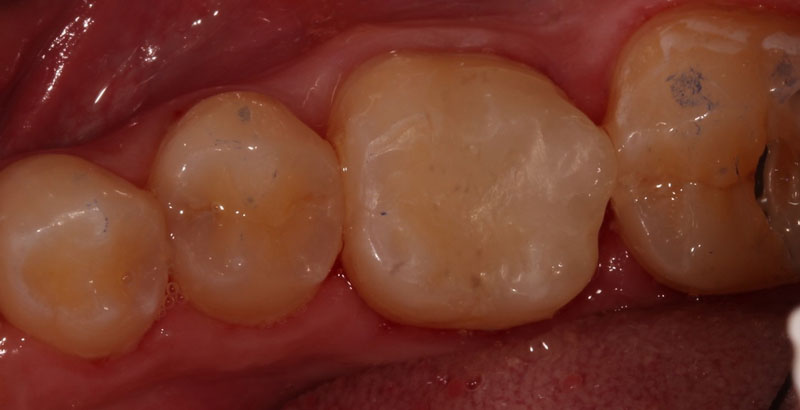

Indirect pulp capping can occur in either a one-step or two-step process. In the one-step process, a medicament is placed in the deepest aspect of the preparation, and the definitive restoration is immediately placed.

In summary, the research shows that we can predictably perform pulp capping procedures using the bioceramic materials currently available.

The endodontic diagnosis determines whether or not we should consider pulp capping for our deep carious lesions. If we have a vital, normal pulp, our chances of successfully maintaining vitality are much greater. However, other treatment options should be considered if we have a symptomatic or necrotic tooth.